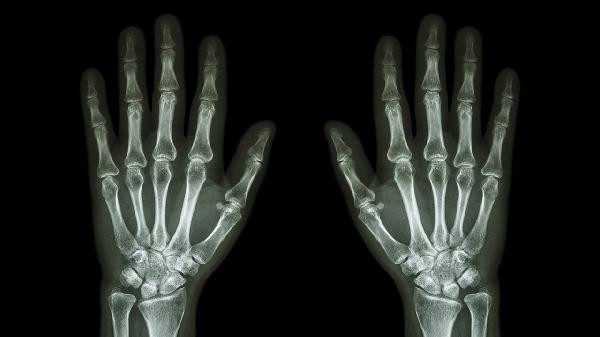

中老年人群多见,与关节软骨退化有关,晨僵时间通常不超过30分钟。X线检查可见关节间隙狭窄。医生可能建议使用硫酸氨基葡萄糖胶囊、双醋瑞因胶囊等软骨保护剂,疼痛明显时可短期用洛索洛芬钠片。严重关节畸形需考虑关节置换手术。